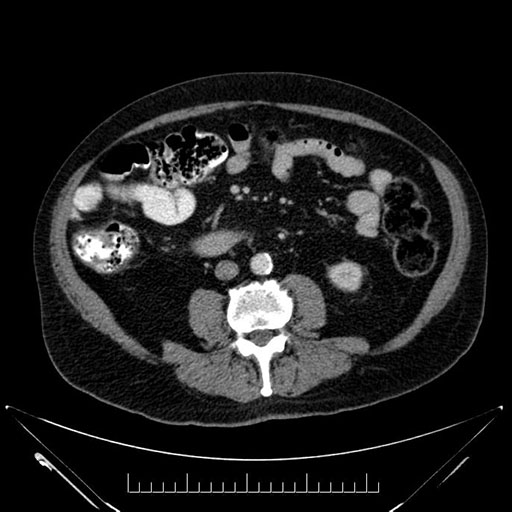

Whipple (pancreaticoduodenectomy) [case 7]

Imaging Analysis

Look through the patient's CT scan to identify any areas of concern for the necessary procedure.

Based on your CT findings, which issue(s) would give reason for "planned slowing down moment(s)" in this case?

Considering a standard Whipple procedure, what step(s) of the operation would you do differently in this case?